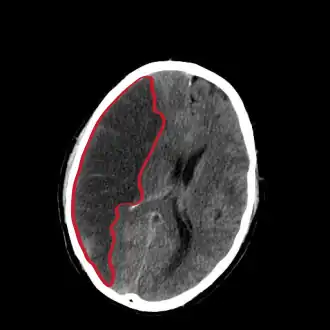

CT-beeld van een herseninfarct rechts (links op de afbeelding). Het donkere gebied is oedeem, met daarin (niet te onderscheiden) necrotisch weefsel. | ||||

In de acute fase is een CT-scan van de hersenen nodig. De CT-scan zal in deze fase het infarct niet kunnen aantonen, maar dient om een hersenbloeding uit te sluiten. Pas als zeker is dat er geen bloeding is, kan begonnen worden met de trombolyse ter behandeling. Alleen als er twijfel is, kan voor een MRI worden gekozen, maar deze heeft als nadeel dat de beschikbaarheid minder groot is en dat het onderzoek langer duurt. Verder wordt altijd bloed afgenomen, wordt de bloeddruk geregeld gemeten en wordt een hartfilmpje (ECG) gemaakt. In de dagen na de beroerte wordt vaak een echo onderzoek (duplex) van de halsvaten gemaakt om vernauwingen (stenosen) aldaar op te sporen.